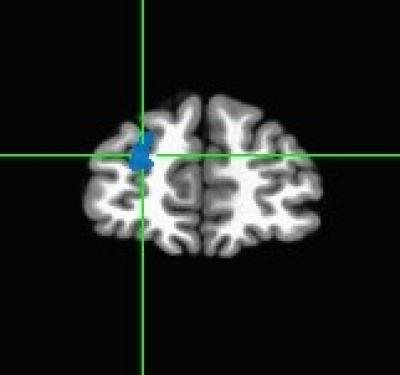

Those in the successful weight loss maintenance group responded differently to these pictures compared to the other groups. Specifically, researchers observed strong signals in the left superior frontal region and right middle temporal region of the brain – a pattern consistent with greater inhibitory control in response to food images and greater visual attention to food cues.